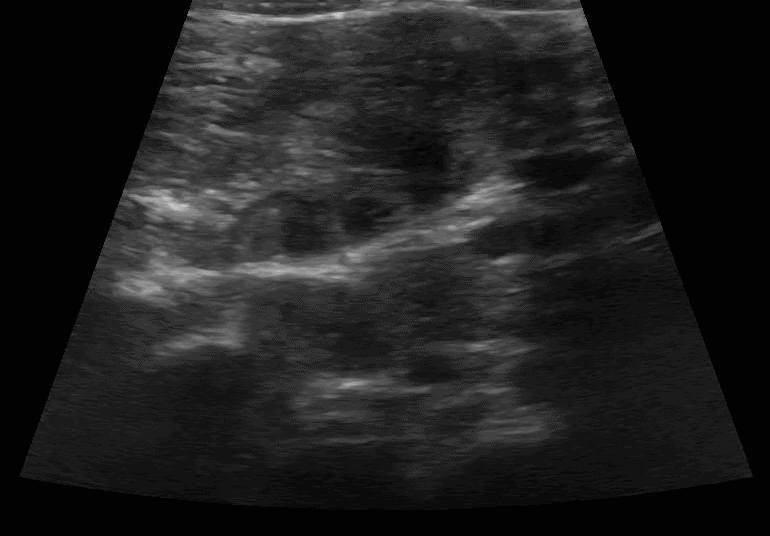

Scanning technique: When evaluating for intussusception with point-of-care ultrasound (POCUS), the infant is placed supine and a high-frequency linear transducer is used initially, with a curvilinear probe available for deeper or larger fields of view. The abdomen is scanned systematically in transverse and longitudinal planes, starting in the right lower quadrant and sweeping through the right upper quadrant, epigastrium, and left abdomen, with particular attention to the periumbilical region and right upper quadrant, where intussusception is most commonly identified. Graded compression is applied to displace bowel gas and improve visualization. On POCUS, intussusception classically appears as a “target” or “donut” sign in the transverse view, characterized by concentric hypoechoic and hyperechoic rings, and as a “pseudokidney” or “sandwich” sign in the longitudinal view. Associated findings may include proximal bowel dilation, free fluid, or absent peristalsis within the involved segment.

Image 1: Intussusception short axis diameter measurements.

Clip 1: Intussusception short axis.